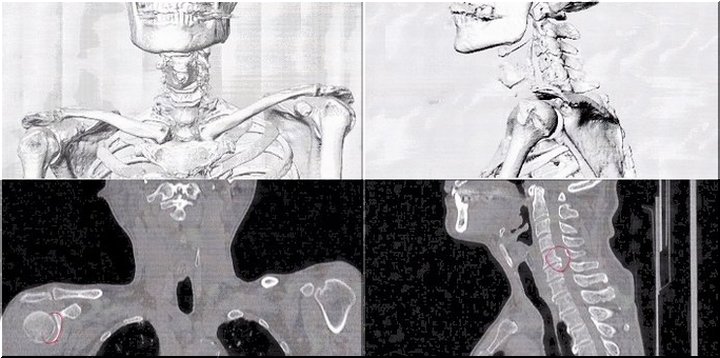

数日前に右腕に激痛が走り、慌てて主治医行きとなりました(^-^;

数日前でしたか…右腕に何となく違和感を感じておりましたが、別に気に掛けておりませんでしたGONsanです。

が、翌日には激痛が走り慌てて主治医行きとなりました(^-^;

とりあえずCTスキャン。

で、頂きましたのが、その一部のこれらの画像なんです(^.-)☆

特に痛みの原因となるようなモノは見当たらず、強いて言えば『老化現象』との事でありました。

痛み止めとシップ薬で痛みが取れなければ、次はMRIとの事でありました(^-^;

…と、こんな記載がWEB上にありましたけど、痛みが取れませんから渋々MRI検査も受ける事に致しました。

と言う訳で、本日がそのMRI検査の実施日でありました。

主治医のクリニックではMRI検査は出来ませんから、紹介先の病院で実施。そしてそのデータを主治医に持参。